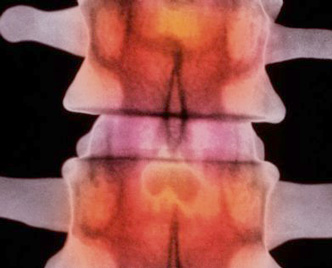

Los científicos aseguraron, que a una paciente de 15 años con grave afección de mielitis, se le hizo más aguda con la infección de zika.VariosPor Freddy ReyesSegún un caso estudiado en Guadalupe (Antillas francesas), reveló que el virus del Zika, que causa microcefalia y síndrome neurológico de...

Los científicos aseguraron, que a una paciente de 15 años con grave afección de mielitis, se le hizo más aguda con la infección de zika.VariosPor Freddy ReyesSegún un caso estudiado en Guadalupe (Antillas francesas), reveló que el virus del Zika, que causa microcefalia y síndrome neurológico de...